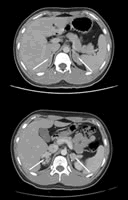

垂体MRI示“垂体微腺瘤可能”;CT示“双肾上腺增生,左肾上腺腺瘤可能”(图1); MIBG示“左肾上腺嗜铬细胞瘤可能”。

肾上腺CT示“双侧肾上腺较前显著增生,右侧为著”(图2);垂体MRI示“垂体未见明显异常”。骨龄片显示骨骺基本愈合,约18岁左右。

图1 肾上腺CT(术前):双肾上腺增生,左肾上腺腺瘤可能

图2 肾上腺CT(术后):双侧肾上腺较前显著增生,右侧为著, http://www.100md.com